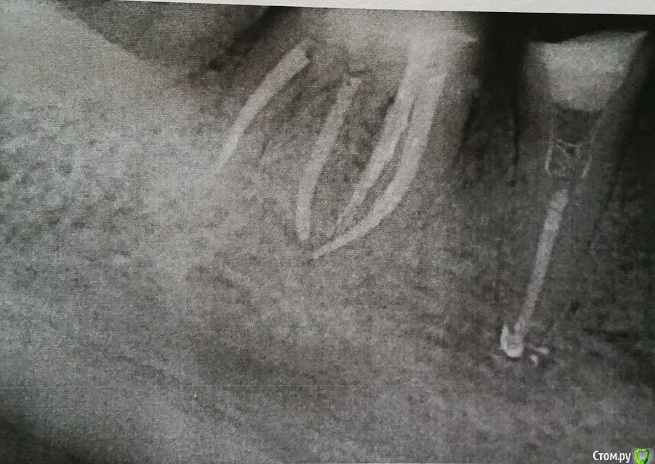

Анна Л. Опубликовано 22 января, 2020 Поделиться Опубликовано 22 января, 2020 Здравствуйте. Готовлю рот к имплантации, новым коронкам..При перелечивании 46 зуб треснул. Предложили гемисекцию.,Сама в раздумьях: её или сразу удалить? 1. Жалко, крепкий, без воспалений. 2. Каналы пролечены. Предложили объединить коронкой с 45. Корень будет (если) удаляться со стороны пятёрки,один из четырёх. Рядом живой 47. Что ещё останавливает от удаления (меня) - уже грядёт имплантация: 15, 35, 36, 11 и 22. А если будет ещё одно удаление, то это оттянет процесс минимум на три месяца, а и так уже времянки и дыры, организм уже устал, суставы.Плюс финансовая нагрузка повышается. Но если гемисекция,то самое большое опасение такое: 1. За пятёрку. Вдруг её потом расколбасит заодно. 2. За кость - может потом не на что будет ставить имплантат? Ну и за прикус. Правильнее вроде всё выставлять сразу. Хотя мостик 46-45 наверное для этого сгодится? Снимок просить постеснялась. Ссылка на комментарий